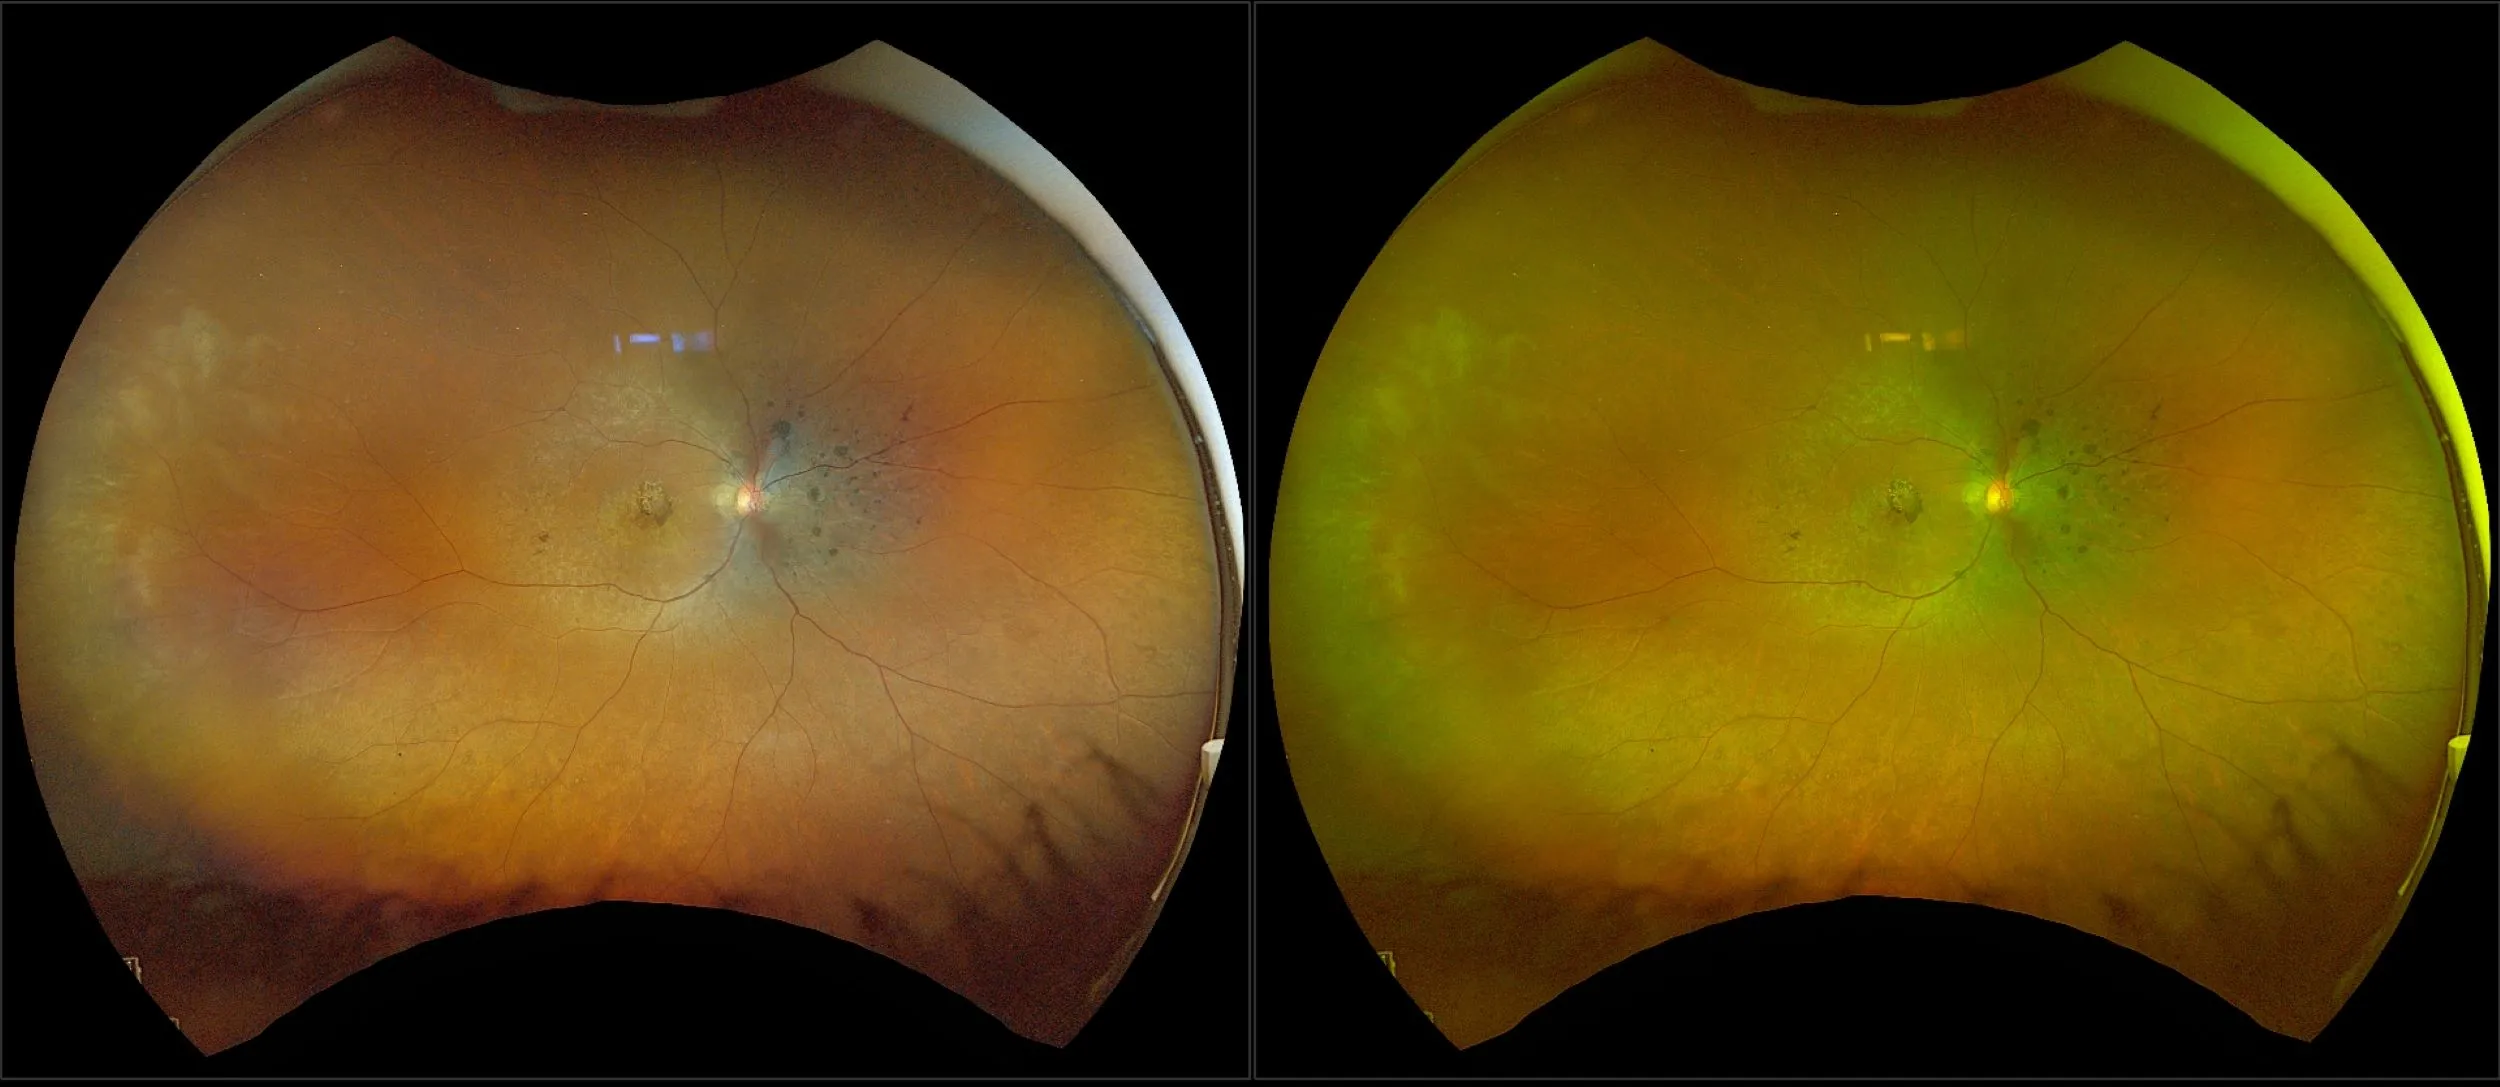

optomap® Recognizing Pathology

This material is designed as a searchable reference resource to support clinical decision-making. The information contained here should be used as general guidance when viewing optomap and OCT images from Optos devices. The differential diagnosis should be made under the direction of the responsible physician. These images were taken on the latest ultra-widefield optomap devices.

The Cases and Images

optomap Recognizing Pathology is searchable by pathology and/or optomap image modality. You may search by multiples of each selection. Each individual case is represented by the accompanying thumbnail image. Most cases include several different optomap image modalities. To view a full description of the case, please click on the thumbnail. Each image in the case will be made available through our OptosAdvance software which provides multi-dimensional visualization of digital images to aid in the analysis of anatomy and pathology. Support and pathology definitions can be found by selecting one of the buttons, above. Should you have questions, please complete the form below.